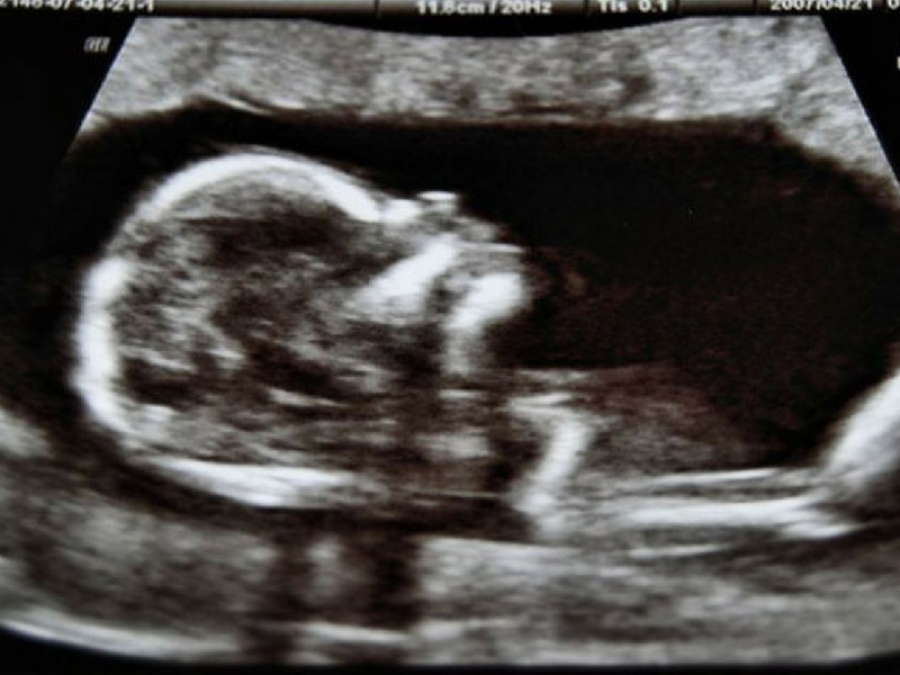

Ecco come si presenta il bambino nel secondo mese di gravidanza: dalla quattordicesima alla ventisettesima settimana, le caratteristiche del piccolo che pian piano continua a crescere

Ma cosa accade nella pancia passati questi primi tre mesi? Innanzitutto, il bambino già alla sedicesima settimana si presenta con le sue piccole unghie, ciglia e sopracciglia, elementi che lo rendono sempre più umano e dolce; oltre a queste, però, vostro figlio in questo periodo inizia a coprirsi di lanugine, una sottile peluria che lo ricopre completamente a che sparirà naturalmente dopo il parto.

Dalla diciassettesima settimana, invece, il vostro piccolo inizia a percepire i primi rumori provenienti dall'esterno del pancione (apparentemente lo fa attraverso la cute e l'apparato osteo-articolare, percependo le vibrazione sonore); e dalla diciottesima possono iniziare a sentirsi i suoi primi, poco percettibili, movimenti. Il motivo è lo spazio: a questa età il bimbo ha moltissimo spazio attorno a lui, e di conseguenza si muove a suo piacimento, approfittando della comodità.

Passando alla diciannovesima settimana, il vostro piccolo feto avrà già formato i suoi denti da latte dietro alle gengive, peserà all'incirca trecento grammi e sarà lungo più o meno dai quindici ai venti centimetri, come un avocado insomma.

Ed eccoci al quinto mese: alla ventesima settimana il feto comincia a sviluppare la vernice caseosa. Cos'è questa astrusa parola? Si tratta di un rivestimento chiaro, una patina biancastra che lo ricopre completamente, in funzione di proteggere la sua delicatissima cute.

Attorno alla ventiduesima settimana ecco che il bimbo sta sviluppando appieno i suoi sensi. E' infatti in questo periodo che si formano le papille gustative e le terminazioni nervose sulla punta delle dita: una feature importantissima, che permette al piccolo di percepire il proprio corpo attraverso il contatto con le pareti uterine, con le varie parti del corpo e con il cordone ombelicale che lo unisce alla mamma.

I suoni ora, alla ventiquattresima settimana (momento nel quale alcuni bimbi riescono a sopravvivere anche in caso di parto prematuro), sono per lui davvero suoni, non più vibrazioni sonore come alla diciassettesima settimana. Non ascolta solo il battito cardiaco della mamma, ma anche la sua voce, così come quella del papà e di chi le sta attorno; ma anche la musica è importantissima: credeteci quando vi dicono di fare ascoltare Mozart già dalla pancia della mamma; le sue melodie prive di ripetitività piacciono ai neonati ma anche al feto, ed è assolutamente vero che favoriscono lo sviluppo dell'intelligenza logica (così come tutta la musica classica – esclusa quella troppo piena di flauti e violini che eccita troppo i bebè).

E' attorno a questo periodo che, oltre a coordinare molto meglio tutti i movimenti, inizia a succhiarsi il pollice: le più fortunate potranno vederlo nell'ecografia!

Certo, nel secondo trimestre si ha più energia: tuttavia siamo già alla venticinquesima settimana e il pancione, ormai non più camuffabile, cresce a dismisura. Ecco che il fiato della mamma si fa quindi un pochino più corto: non preoccupatevi, è solo il vostro utero che inizia a premere contro il diaframma.

Dalla venticinquesima alla ventisettesima settimana, dunque, si va verso la fine del secondo trimestre, per entrare nell'ultimo periodo passato con il pancione. In queste settimane tutti gli organi interni sono finalmente formati, la pelle del bambino si fa sempre più opaca (prima era un po' più liscia) e vostro figlio raggiunge una dimensione di circa trenta, trentaquattro centimetri: mica male, no?

Foto Credits: https://it.wikipedia.org/wiki/Ecografia_ostetrica